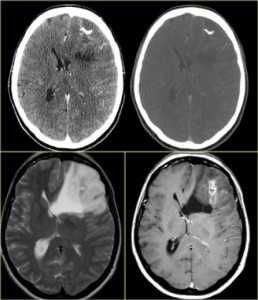

![central_neurocytoma_4]()

Эпендимома в виде солидного образования в правом боковом желудочке (головка стрелки на рис.685). Папиллома сосудистого сплетения в центральном отделе левого бокового желудочка (звёздочка на рис.686), окруженная перифокальным отёком (головки стрелок на рис.686). Субэпендимома левого бокового желудочка (стрелки на рис.687).

Субэпендимарная гигантоклеточная астроцитома (рис.688) встречается исключительно у пациентов с туберозным склерозом и интенсивно накапливают контраст.

Астроцитомы редко располагаются в желудочковой системе (рис.689).

Интравентрикулярные менингиомы (рис.690) имеют гомогенное контрастирование с определением чётких ровных контуров.

![central_neurocytoma_5]()

Субэпендимарная гигантоклеточная астроцитома с типичным расположением в области отверстия Монро (головка стрелки на рис.688). Астроцитома, растущая из прозрачной перегородки экзофитно в просвет правого и левого бокового желудочка (головка стрелки на рис.689). Внутрижелудочковая менингиома в центральном отделе левого бокового желудочка (звёздочка на рис.690), сопровождающаяся перифокальным вазогенным отёком прилежащего белого вещества перивентрикулярной зоны (головки стрелок на рис.690).